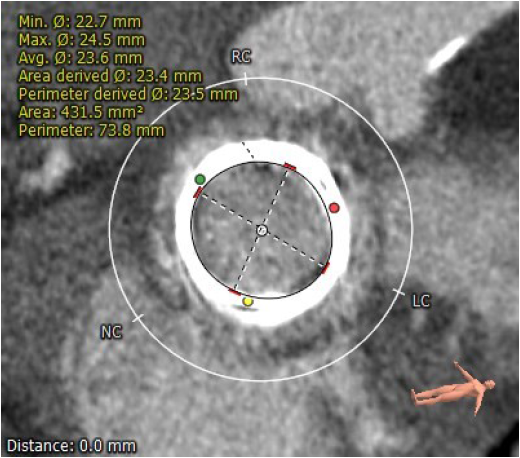

术前CT评估

生物瓣瓣环内径23.5mm

生物瓣瓣环外径29.5mm

生物瓣环周围无明显钙化

生物瓣瓣架高度16.1mm